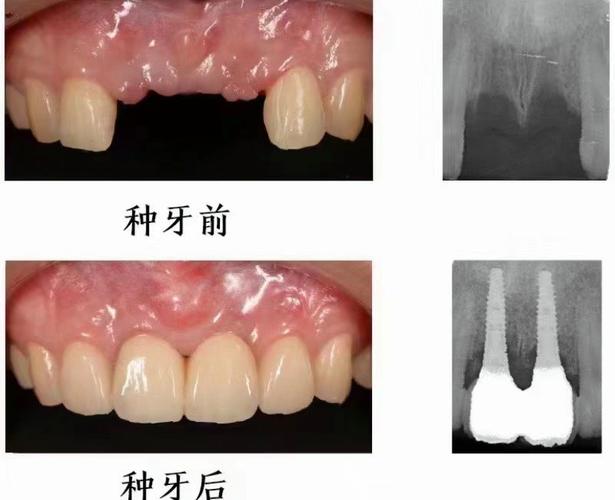

门牙位于口腔前部,不仅承担切割食物的功能,更对面部美观和发音至关重要,当门牙区域出现三个相邻牙齿缺失时,种植修复是理想的修复方式之一,但能否种植、如何种植需结合具体口腔条件综合判断。

针对“门牙相连三个缺失”,种植方案需根据缺牙位置(如中切牙、侧切牙、尖牙连续缺失)、骨量、患者美观需求等制定,常见方案如下: